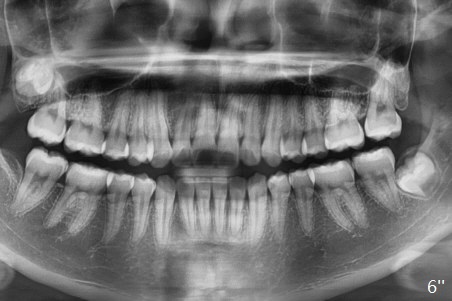

A 12-year-old woman has severe crowding including UL7 impaction (Fig.1-5), finishes non-extraction orthodontics at the age of 15 (Fig.1'-5') and returns for retainer remake at 19 (Fig.1''-5''). Four years post debanding, UL7 (Fig.4') seems to improve its position (Fig.4'').